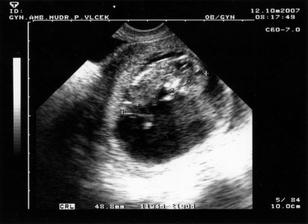

Náš svatební den byl 7.7.2007 a mimísek na sebe nenechal dlouho čekat 🙂 Už 21.8.2007 jsme na testu objevili // a těhu průkazku jsme dostali 12.10.2007. Naše bublinka by se měla narodit na konci dubna, tak uvidíme, kdy se jí bude chtít na svět.